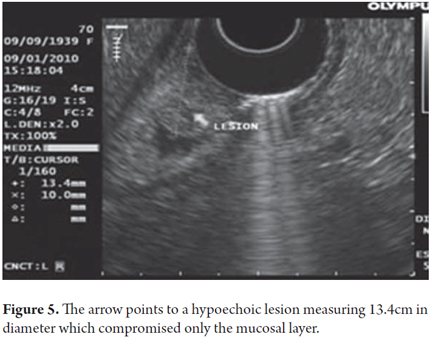

Upper endoscopy was performed on a 75 year old patient who had developed dyspeptic symptoms without any prior warning signs. A raised20 mm lesion found in the prepyloric region was classified as a type 0-I lesion (Figure 3). Endoscopic mucosal resection performed with the lift and cut with loop method achieved complete removal without complications (Figure 4). A previous endoscopy had shown compromise by a tumor in only the first two ultrasound layers i.e. the mucosa (Figure 5). The pathology report indicated a well-differentiated adenocarcinoma with lateral edges and depths that were negative for a tumor (Figure 6).

In this other case a raised lesion in the anterior wall of the mid-corpus (Figure 7) can be seen. It was reported as a well-differentiated adenocarcinoma. An endoscopy showed that the lesions compromised only the first two ultrasound layers (mucosa) (Figure 8).